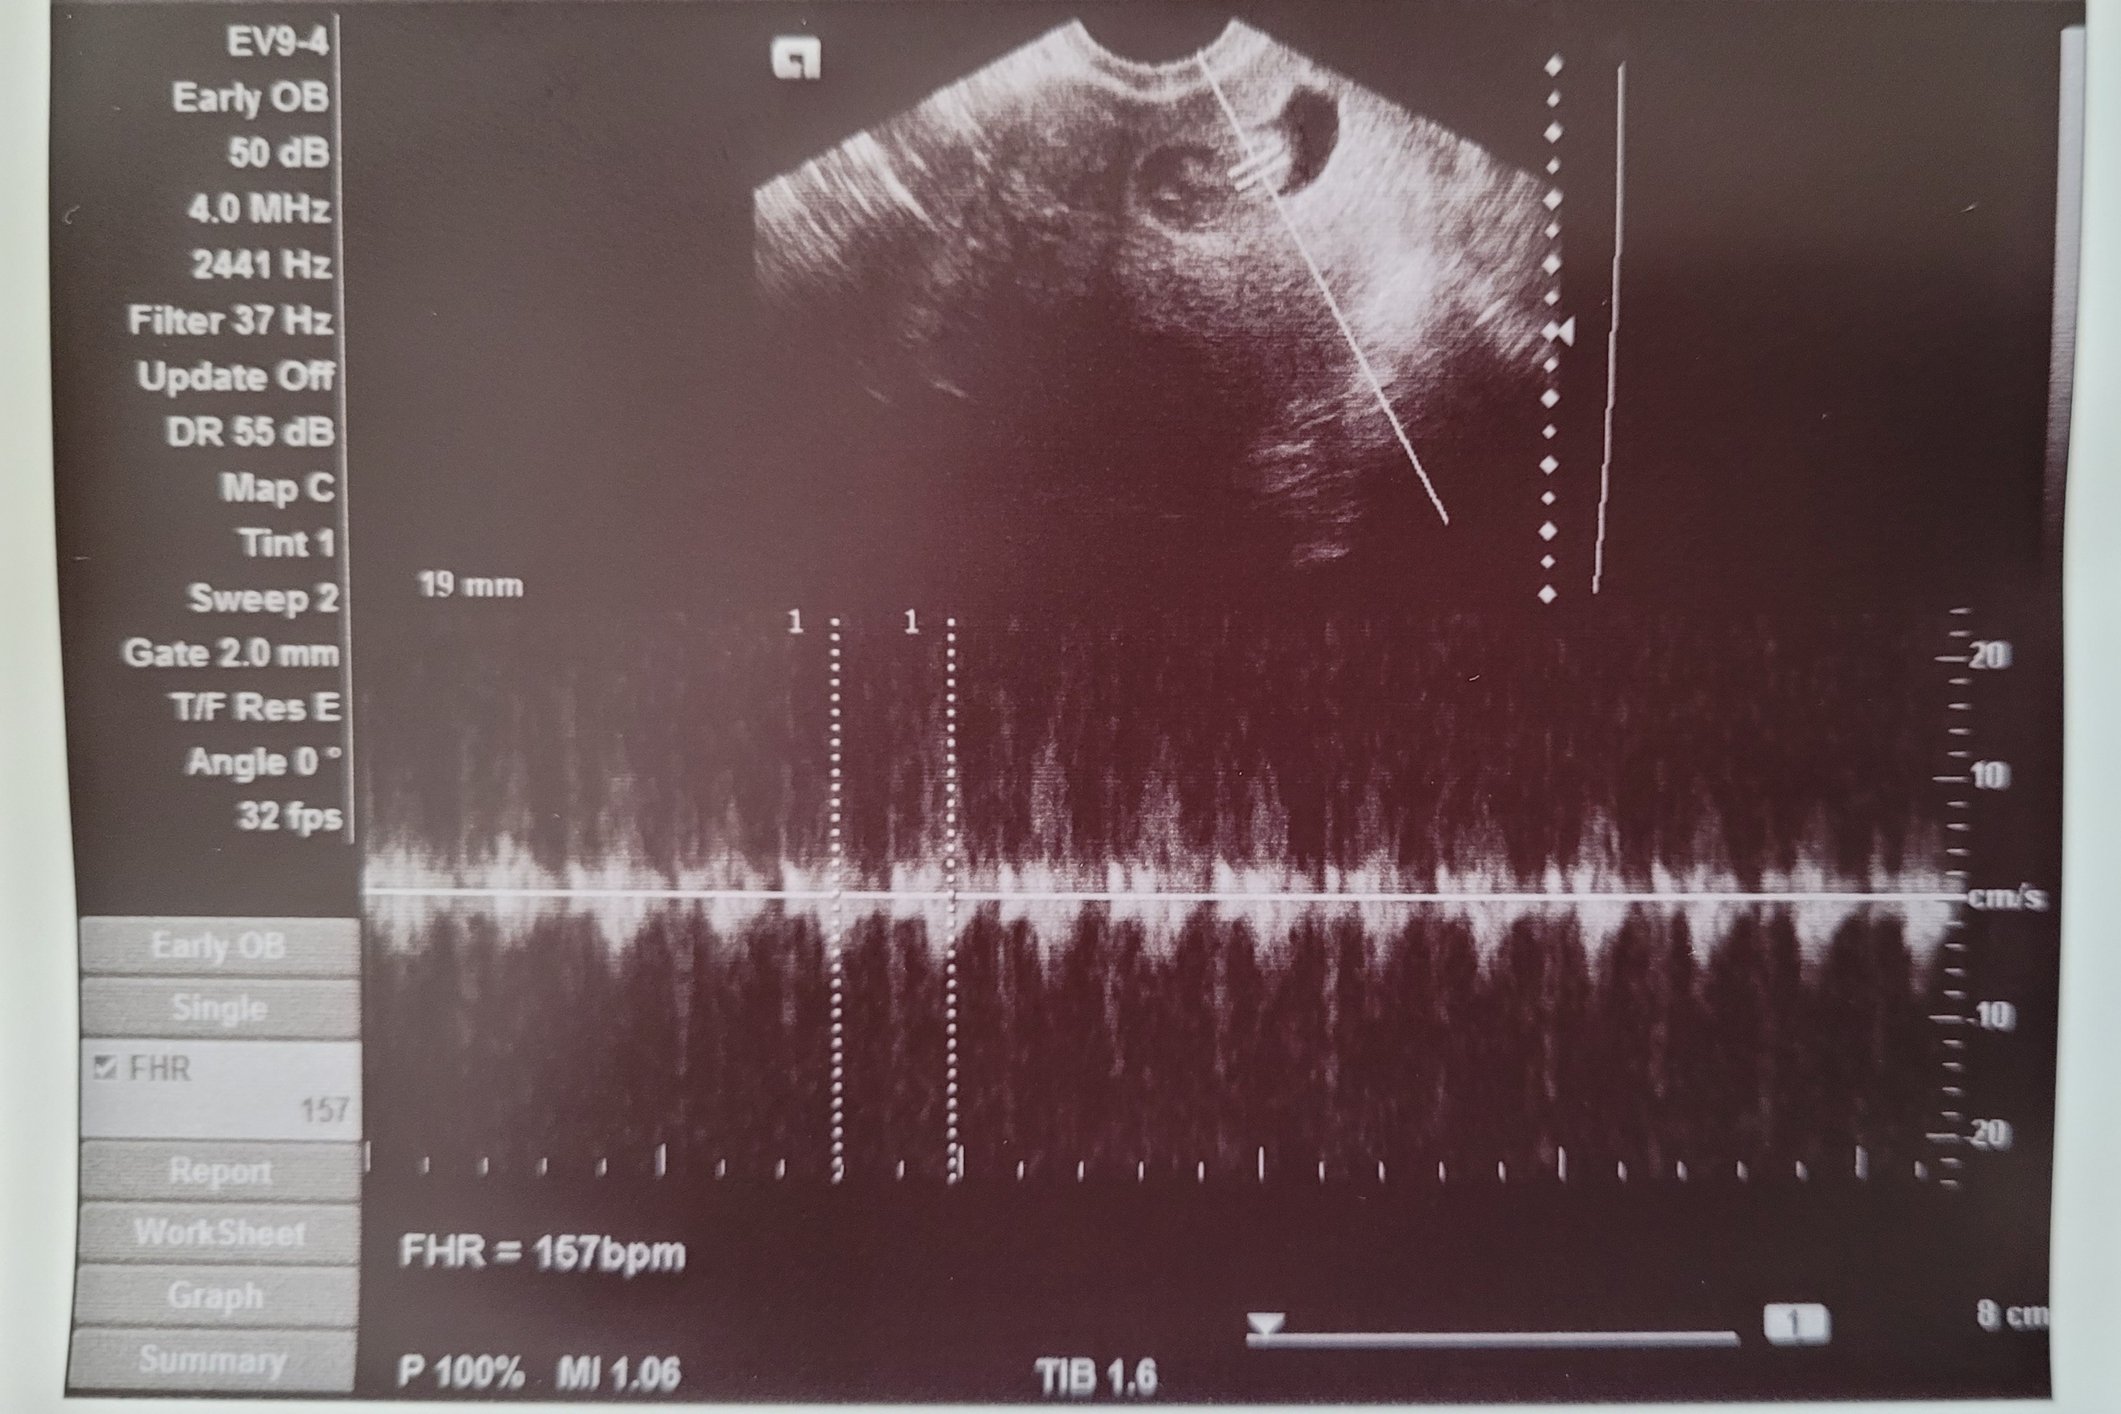

I have had three early miscarriages and at least two were blighted ovums so I was not expecting a positive test and DEFINITELY wasn’t expecting to see a heartbeat but here we are holding strong at 6 weeks 2 days!

Still early so with my history I’m not out of the woods but I have never seen a baby or heartbeat in my previous pregnancies, so I am very cautiously optimistic.